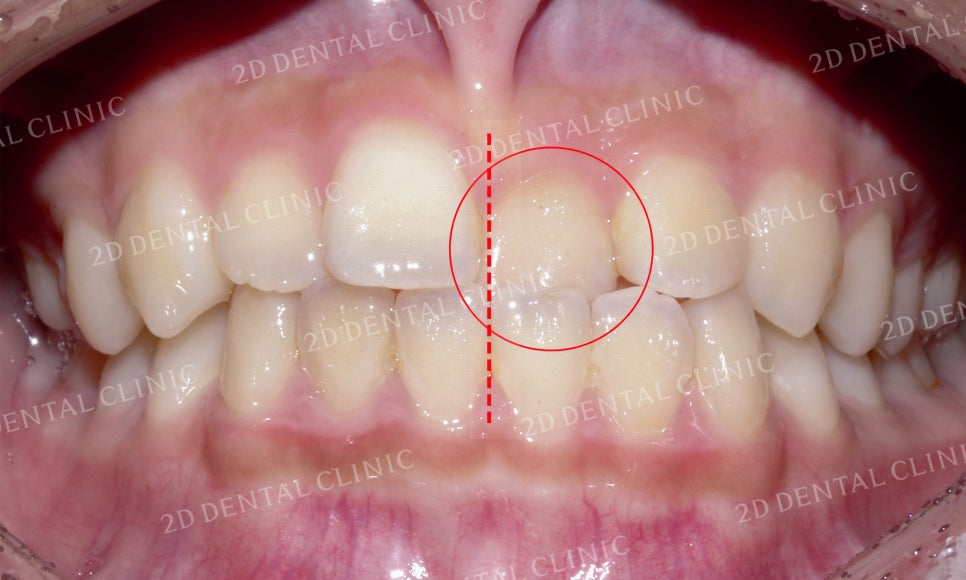

미소 시 치아의 사진입니다.

좌측의 중절치를 보시면

정상적인 교합과 달리

상악의 치아가 하악의

안쪽으로 물리고 있는데요,

이러한 교합 상태를

'반대교합'이라고 합니다.

전치부의 치아들을 자세히 살펴보면

상악 좌측 중절치의 반대교합 영향으로

상하악의 정중선도 틀어진 모습인데요,

이러한 문제들로 상악의 절단연 또한

삐뚤삐뚤한 모습입니다.